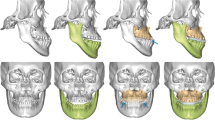

To transfer the 3D planning to actual surgery (Figs 3 and 4), measurements in maxillary pillars bilaterally, face bow-based midline checking (nasal dorsum and tip, lips, maxilla, dental arches, and chin areas), and middle and lower facial third proportions judgments were used as reference. The splitting of BSSO was carefully accomplished to avoid injury to the inferior alveolar nerve (Fig. 3). The maxillomandibular complex with final surgical splint was moved to the desired position (Fig. 4). After Le Fort I fixation with miniplates and screws, the proximal ramus segment was placed in a relaxed position and gently pushed up to ensure the position of the condylar head in the glenoid fossa. Using the 3D simulated image as a guiding template, the desired relationship between the proximal and distal segments was achieved. Percutaneous insertion of 3 bicortical screws 14–16 mm long was performed in the ramus. No interpositional bone graft was used in procedures requiring maintenance of intersegmental gaps. Intermaxillary fixation was released and the occlusion was evaluated. Genioplasty was finally executed as planned, along with intraoperative judgement.

Single-splint two-jaw orthognathic surgery-based skeletofacial reconstruction principle. (a) Both maxilla (Le Fort I segment) and mandible (two proximal ramus segments and one distal segment) were completely osteotomized, fixed in the final occlusion (surgical occlusion splint), and moved as an integrated “maxillo-mandibular complex” (MMC) to the 3D-simulated position. To transfer the virtual simulation to actual surgery, the MMC was moved in six potential directions, including pitch, roll, and yaw rotations (blue arrows) and en-bloc linear horizontal (left or right shifts and advancements or setbacks in the antero-posterior direction) and vertical (extrusion or intrusion) movements (green arrows).